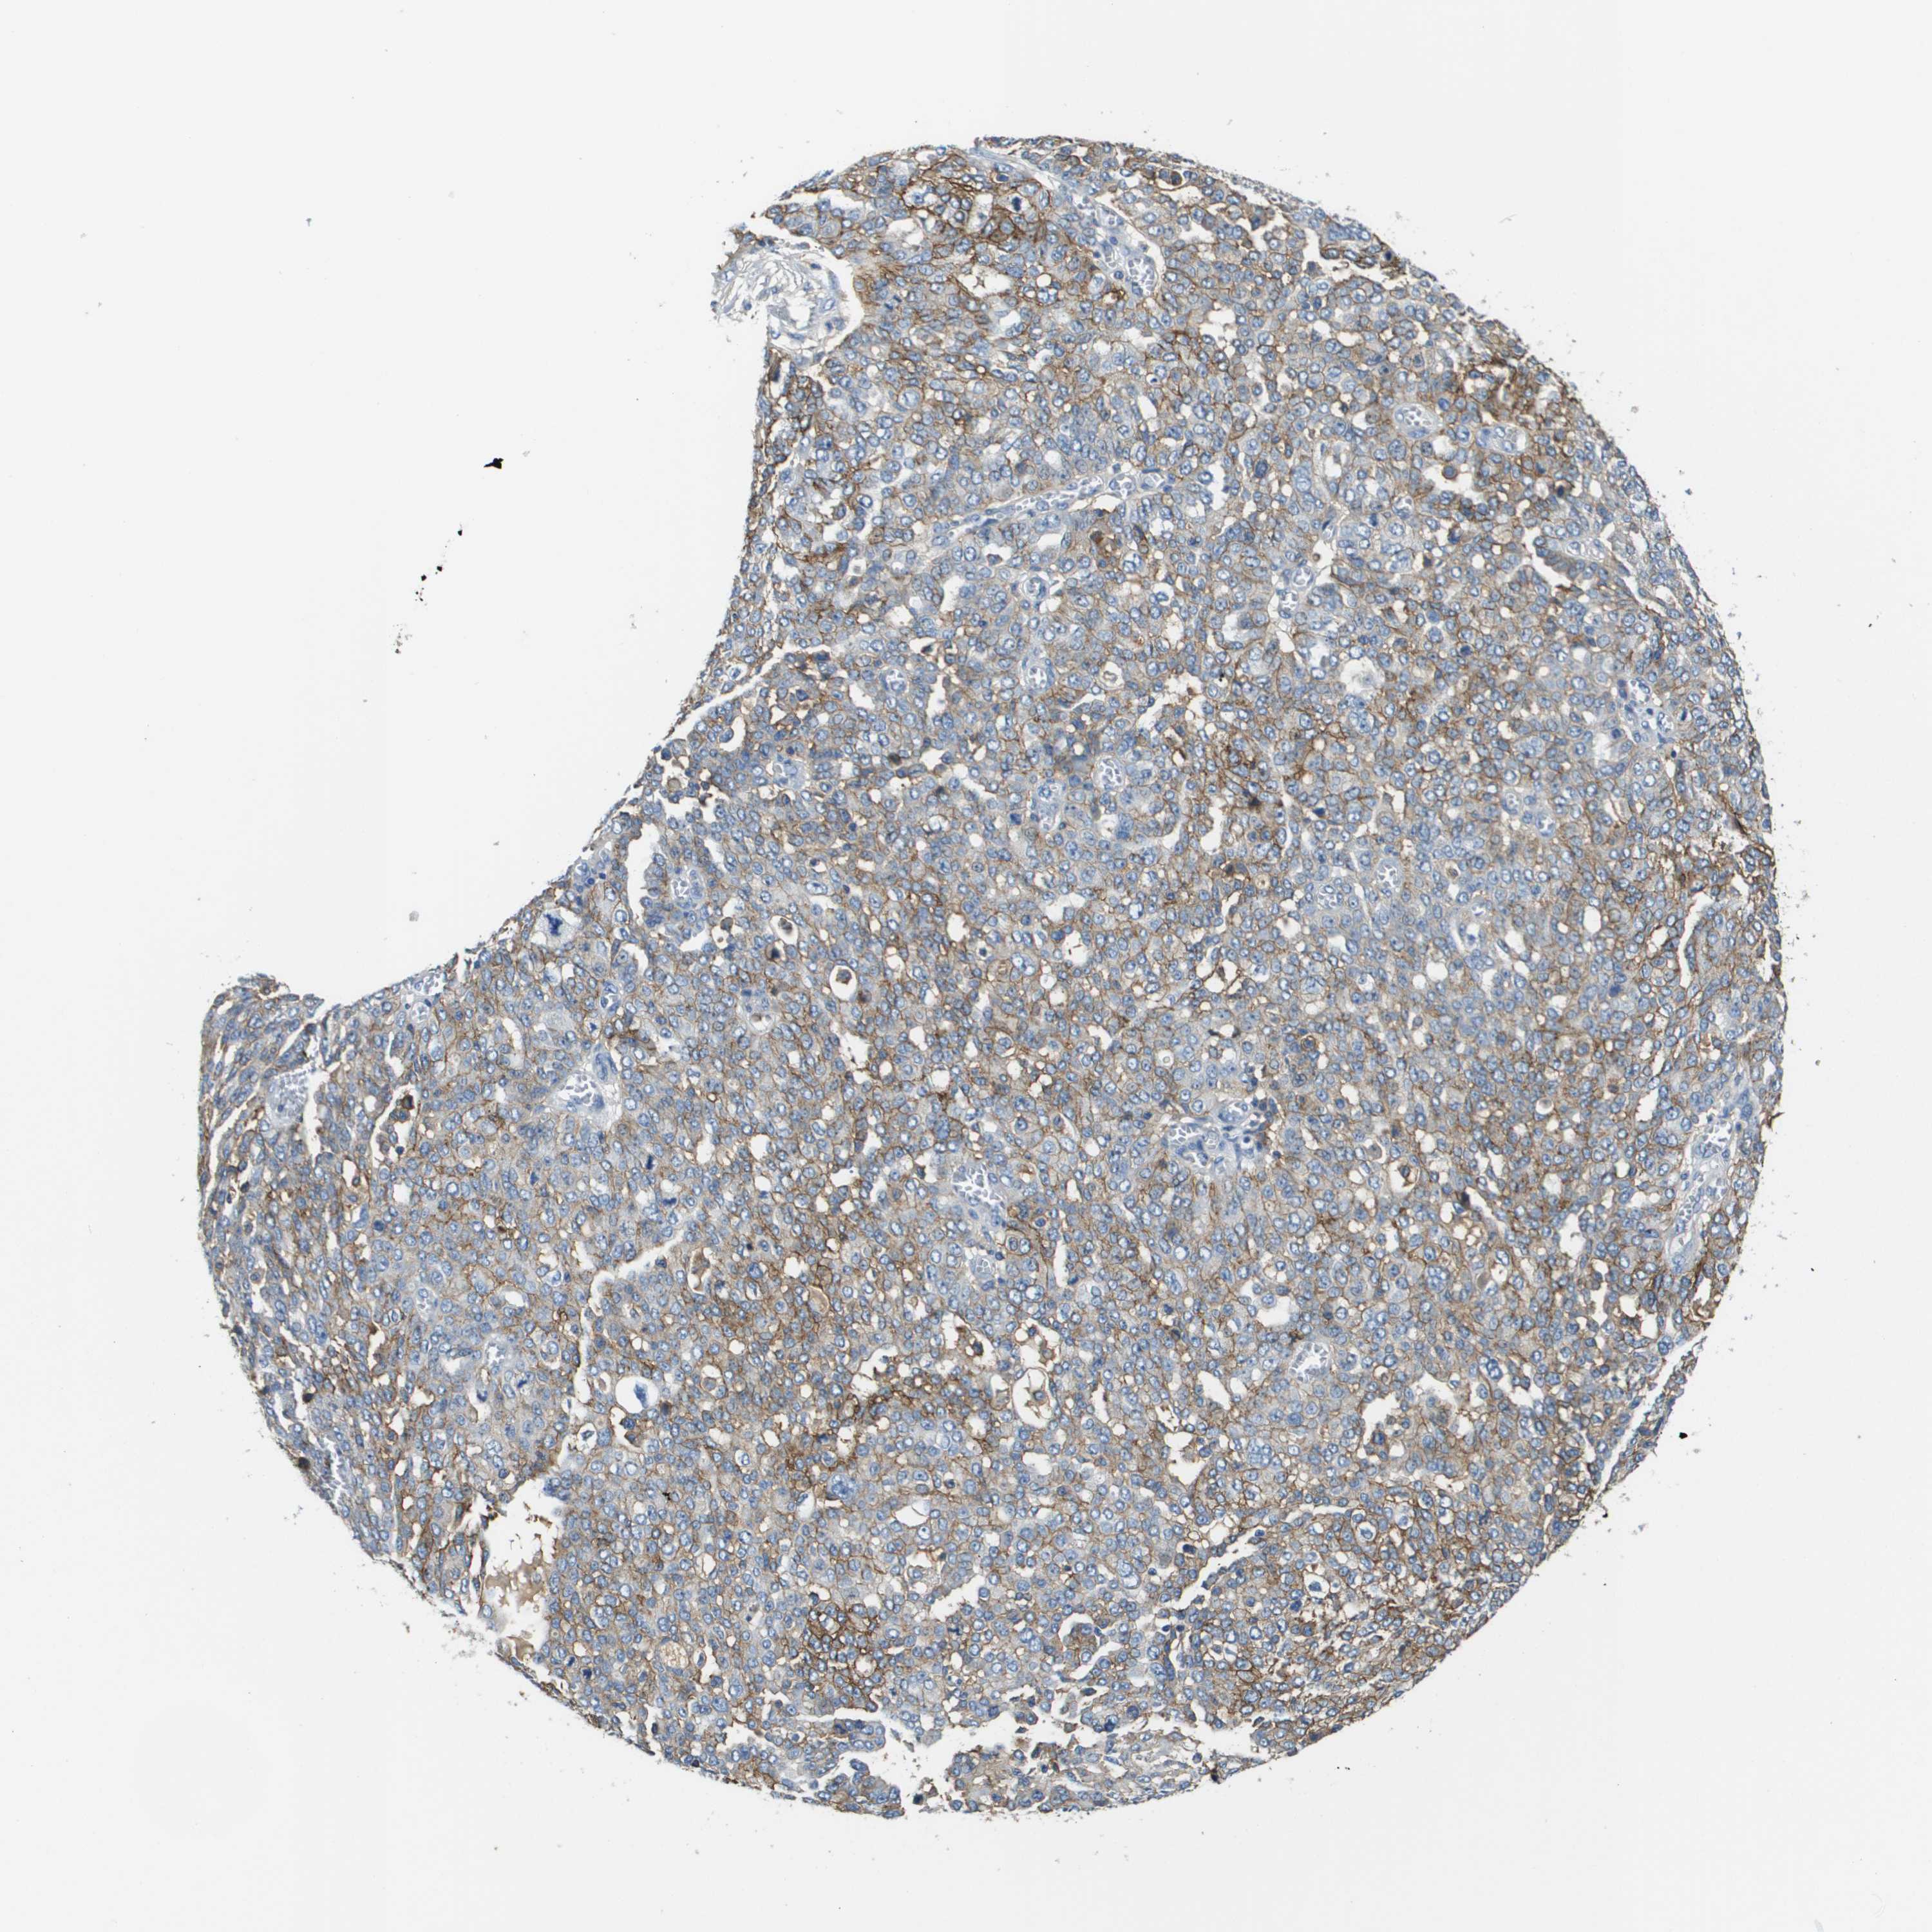

OVARIAN CANCER - Protein expressioni

A mouse-over function shows sample information and annotation data. Click on an image to view it in a full screen mode. Samples can be filtered based on level of antibody staining by selecting one or several of the following categories: high, medium, low and not detected. The assay and annotation is described here.

Note that samples used for immunohistochemistry by the Human Protein Atlas do not correspond to samples in the TCGA dataset.

Antibody stainingi

Antibody staining in the annotated cell types in the current human tissue is reported as not detected, low, medium, or high, based on conventional immunohistochemistry profiling in selected tissues. This score is based on the combination of the staining intensity and fraction of stained cells.

Each image is clickable and will lead to virtual microscopy that enables deeper exploration of all samples and also displays staining intensity scores, fraction scores and subcellular localization as well as patient and tissue information for each sample.

Antibody HPA021451

Antibody CAB017490

Cystadenocarcinoma, serous, NOS

Carcinoma, endometroid

Cystadenocarcinoma, mucinous, NOS

Carcinoma, NOS